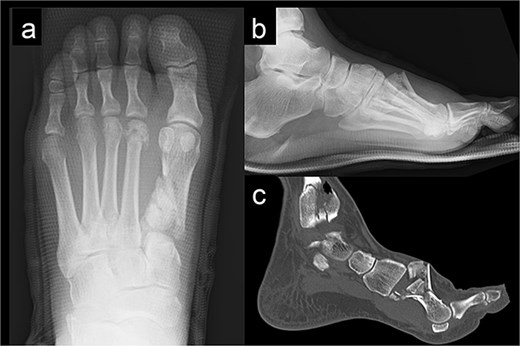

A 52-year-old man presented to our hospital with pain in the left ankle and forefoot after his left foot was caught in a wall while operating a tiller. Deformity was observed in the left ankle joint and the left forefoot. No evidence of neurovascular injuries or wounds was observed. The patient had a history of diabetes and hypertension. Radiography showed fractures of the left first metatarsal (Fig. 1a and b), tibial pylon, and distal fibula. Computed tomography (CT) revealed that the base of the first metatarsal was comminuted (Fig. 1c), and a dorsal skin prominence was identified due to a displaced dorsal fragment.

Radiography (a, b) and computed tomography (c) images of the left forefoot showing the comminuted first-metatarsal fracture.